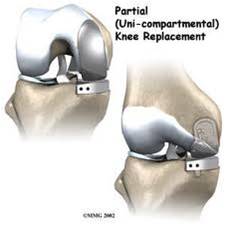

Resurfacing one, two or three cpmpartments is partial knee replacement.

- Unicompartmental knee arthroplasty(UKA)

REPLACE ONLY THE PART WHICH IS DEFECTIVE

NO FUTURE OPTION IS LOST, ALL BONE PRESERVED